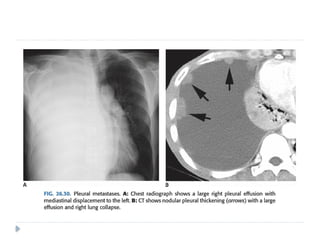

PLEURAL METASTASES

⚫ Adenocarcinomas are known to cause pleural

metastasis than any other histological types of

cancers.

⚫ Common primary sites are from : lung, lymphoma,

and ovary, invasive thymoma

⚫ Pleural effusion is the most common finding on

imaging .